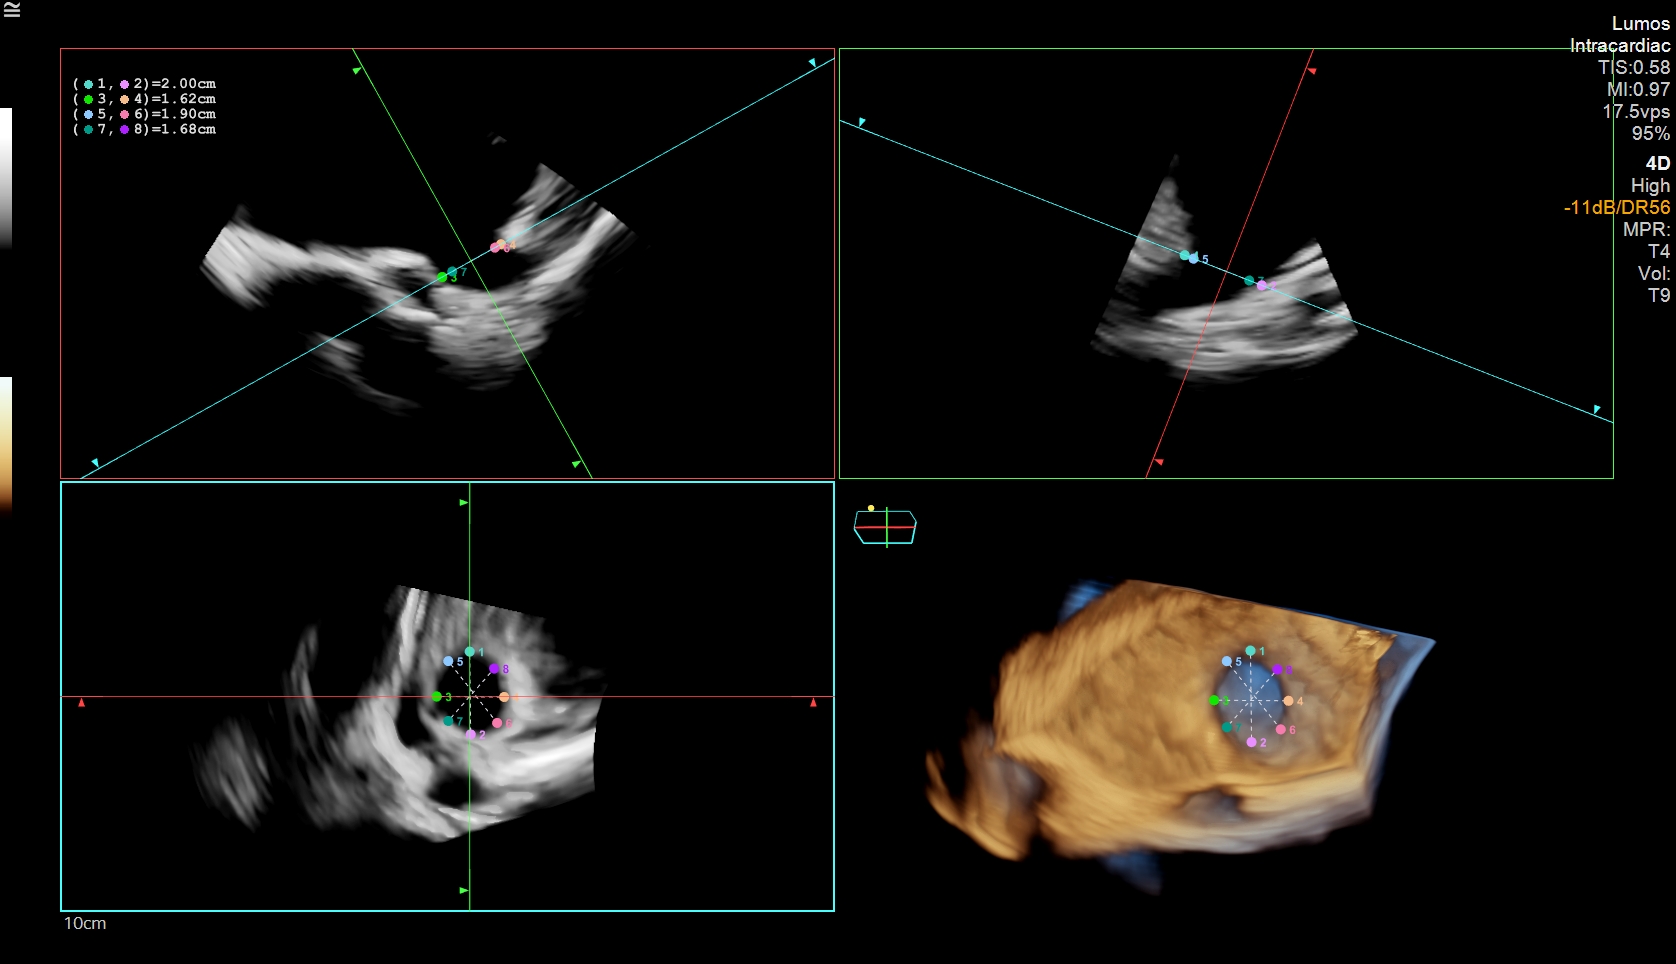

In this case, an elderly female with persistent atrial fibrillation and elevated stroke risk presented for left atrial appendage occlusion (LAAO) evaluation. Due to geographic and logistical challenges in accessing TEE under sedation, the care team opted for a 4D ICE-guided (AcuNav Lumos, Siemens Healthineers) LAAO procedure performed with conscious sedation. Multiplanar reconstructions (MPRs) from 4D ICE were used to assess the LAA’s landing zone dimensions, enabling precise device sizing (Figure 1).

Final 4D ICE imaging confirmed optimal device placement, with no significant peri-device leak, thrombus, or malposition (Figure 4). The procedure was completed without general anesthesia and no complications. The patient was discharged the next day with dual antiplatelet therapy and scheduled follow-up.